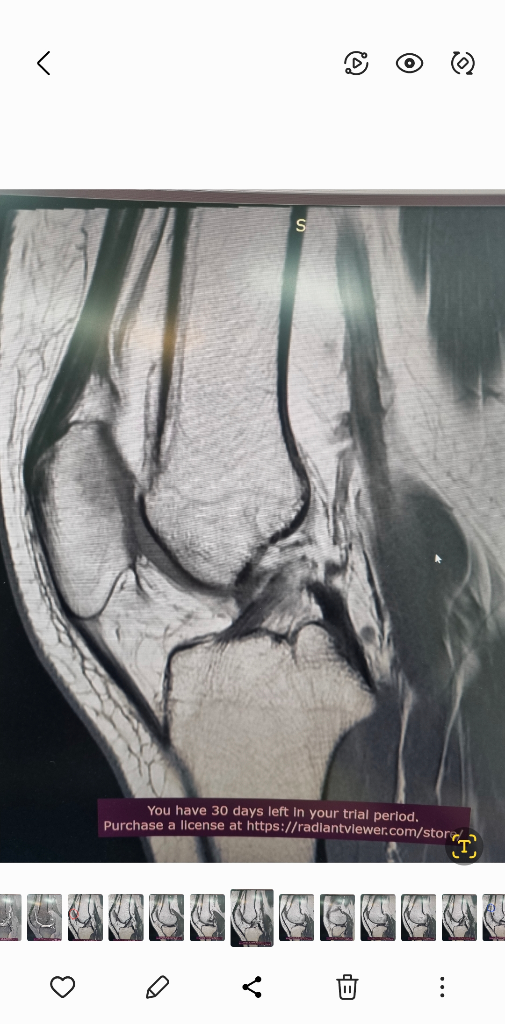

1. 추벽이 아닙니다.

2. 슬개골 관절면에 외상으로 인한 골수부종입니다.

3. 관절면 손상여부는 첨부해주신 영상만으로 알 수 없습니다